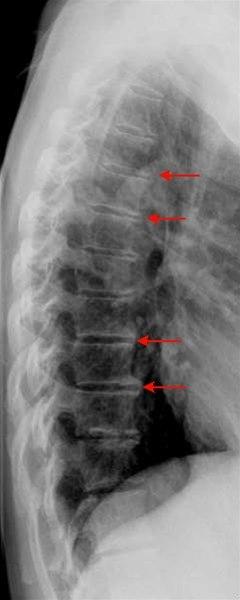

Sidebilde av thoracalcolumna med slitasjeforandringer i form av randpåleiringer, det vil si forkalkninger langs kanten av ryggvirvlene (piler)